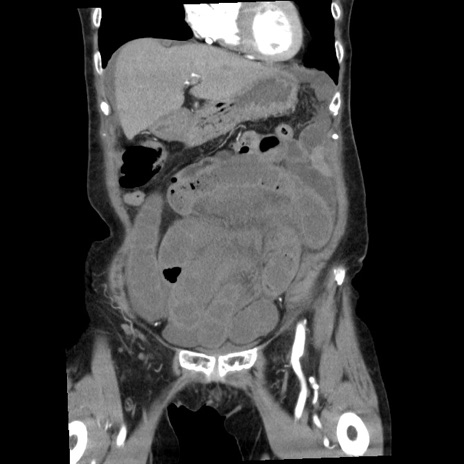

横断像

矢状断像